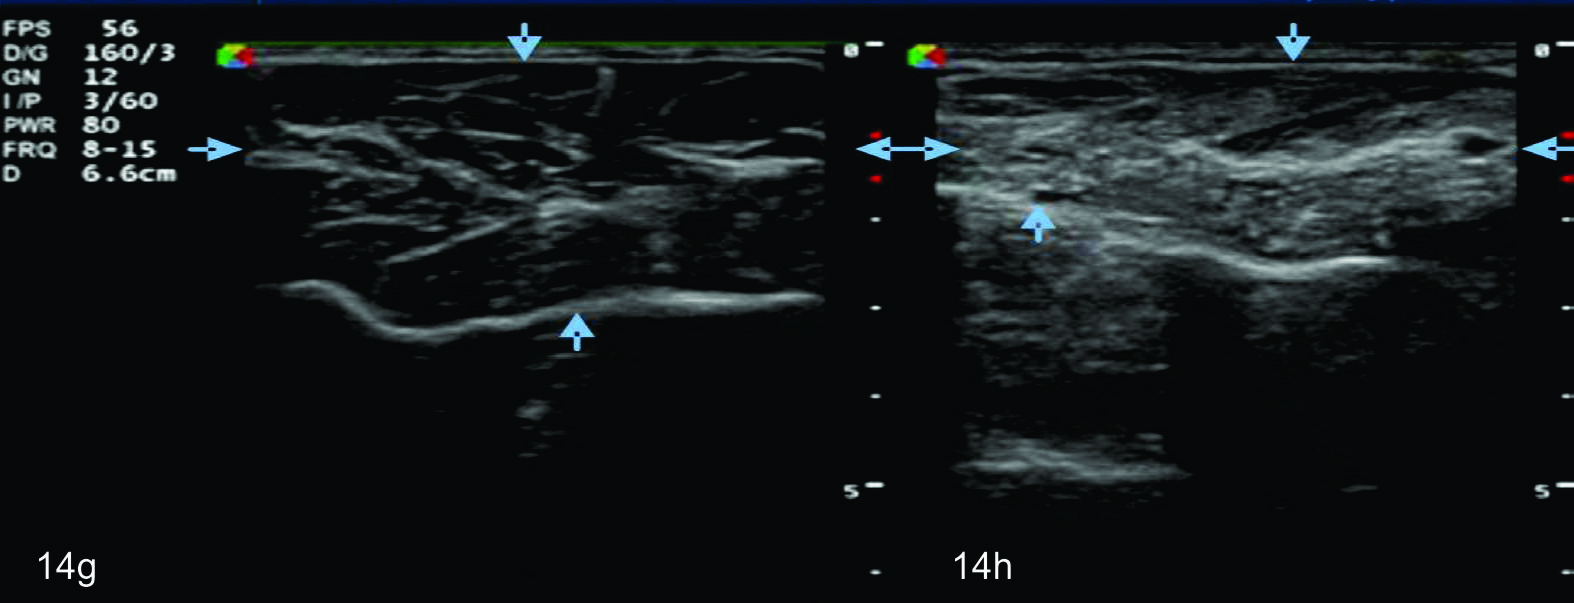

Figura 8

Nervio mediano

Serie de cortes axiales del nervio mediano desde su origen a nivel del hueco axilar hasta el sector distal del antebrazo previo a su ingreso al túnel del carpo. Se identifica el mismo señalado por flechas amarillas y con la palabra mediano. AA-arteria axilar, VA- vena axilar, AH- arteria humeral, VH- vena humeral, VB- vena basilar, AC- ateria cubital, VC- vena cubital, BA- músculo braquial anterior, PR- músculo pronador cuadrado, FS- músculo flexos superficial, FP- músculo flexor profundo, PC- músculo pronador cuadrado. A- axila, se identifica el nervio superfical a la arteria axilar, B- tercio medio del brazo en canal bicipital medial, lateral a la arteria humeral, C- codo, medial al tendón distal del bíceps braquial y a la arteria humeral luego de cruzarla, superficial al músculo braquial anterior, D-antebrazo sector cefálico, entre las dos cabezas del pronador redondo, E- tercio medio del antebrazo, entre los músculos flexor superficial y profundo F- tercio distal antebrazo, superficial al pronador cuadrado.